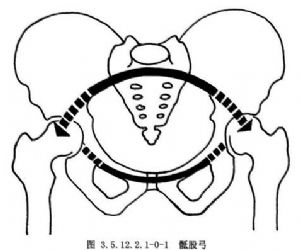

骨盆環分前後兩部分:後部是承重主弓,直立位時重力線經骶髂關節至兩側髖關節爲骶股弓(圖3.5.12.2.1-0-1);坐位時重力線經骶髂關節至兩側坐骨結節爲骶坐弓(圖3.5.12.2.1-0-2~3.5.12.2.1-0-7)。骨盆內血管十分豐富,盆壁動靜脈支緊貼盆壁而行並相互吻合成環。盆腔臟器有伴其動脈的靜脈支和異常豐富的靜脈叢(圖3.5.12.2.1-0-8,3.5.12.2.1-0-9)。後者又多圍繞盆腔內壁,且相互通連。骨盆骨折時易使鄰近的血管損傷而引起大出血,除形成盆腔血腫外,出血量大者還將沿腹膜後間隙向上擴展,形成巨大的腹膜後血腫,引起腹膜刺激症狀。此外,骨盆主要由松質骨構成,血液供應很豐富,骨折斷面可大量滲血,骨盆後壁骨折和骨盆的多發骨折尤易併發大量出血。